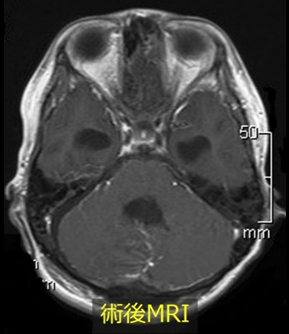

小児における代表的な脳腫瘍であり、ほとんどが小脳に発生します。ふらつきなどの小脳失調に加えて水頭症による頭蓋内圧亢進症状が現れることがあります。

以前は治癒困難な脳腫瘍でしたが、手術手技の向上や放射線治療・化学療法の進歩によって治療成績は確実に向上しています。手術でできる限り腫瘍を摘出し、全脳全脊髄への放射線照射と化学療法を追加することが標準治療となっています。